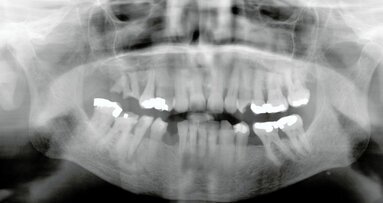

De vraag of een derde molaar eruit moet of niet, is vaak niet gemakkelijk te beantwoorden. Maar door zorgvuldige diagnostiek, een goede risico-inschatting, ...